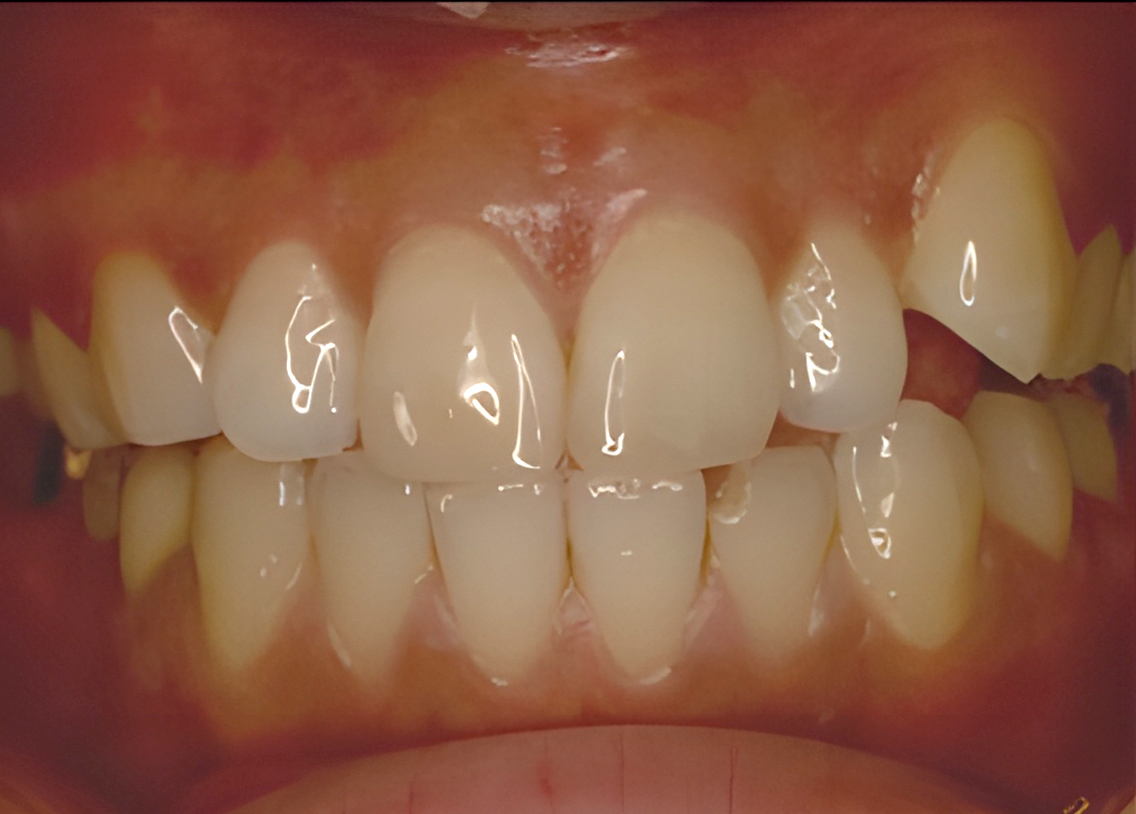

If you are suffering from a wide range of mouth or dental issues, or one specific issue that threatens to cause more issues to arise in the future, you may need to consider a full mouth rehabilitation.

The plan for full mouth rehabilitation may include a combination of treatments, such as implants, crowns, gum treatment, other restorative procedures, and in some cases orthodontic treatment.

Based on the assessment results from a comprehensive examination, our dental specialist will create a customized treatment plan to address your specific dental needs.

Before Treatment

Implant Placed

Restorations

Completed